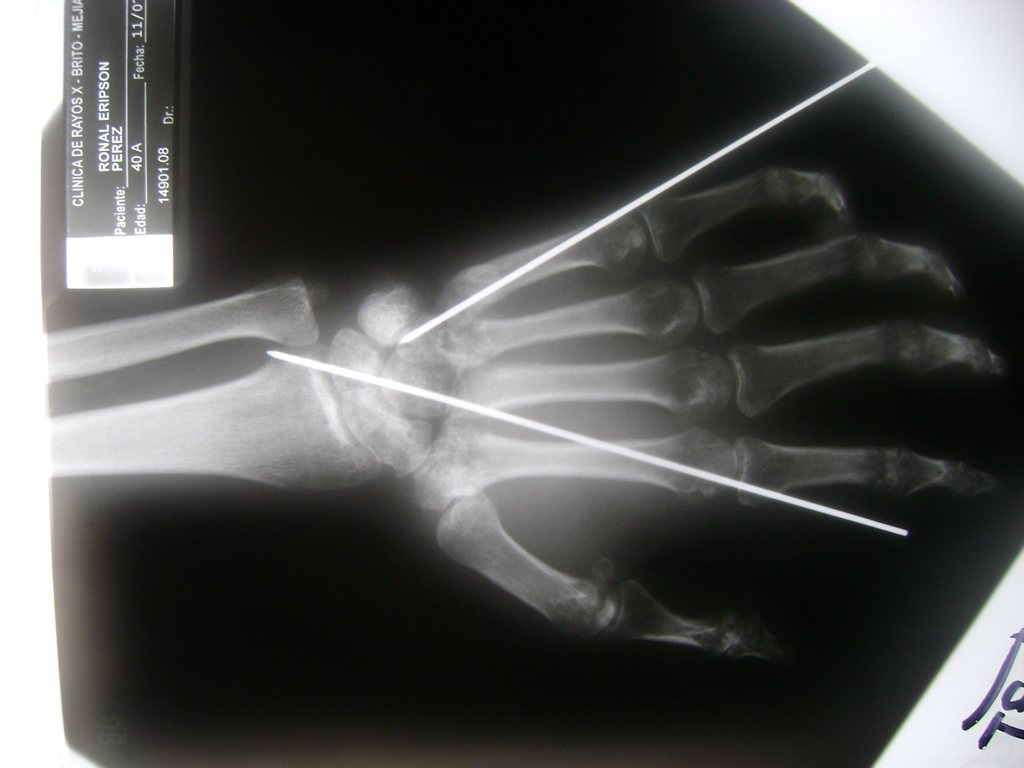

Cirugías de Húmero - Cirugías de Muñecas y Manos

Los procedimientos más comunes en cirugía de la mano son aquellos destinados a reparar traumatismos, incluyendo lesiones de tendones, nervios, vasos sanguíneos, y articulaciones; huesos fracturados; y quemaduras, cortes, y otros daños de la piel.